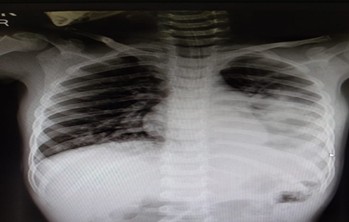

On arrival at the emergency room, the child was drowsy but hemodynamically stable, with tachypnea, hypoxemia, SPO2 88%, Temp 101.20 Bilateral subcostal retractions, and reduced air entry over the left lung. Chest X-ray suggested aspiration pneumonitis, more prominent on the left, following thinner ingestion. The child was kept nil per oral, started on oxygen, and shifted to the PICU for close monitoring. Lung POCUS revealed left basal consolidation with bilateral lower-lobe B-lines. With supportive care, antibiotics, steroids, and respiratory support, the child showed steady clinical and radiological improvement. Respiratory support was weaned within 48 hours, feeds were gradually resumed, and the child became alert, afebrile, and stable. Residual left lower-zone consolidation persisted on follow-up POCUS, but the child tolerated oral feeds well and was discharged in stable condition with appropriate medications and advice

Fig (1): Chest X- ray – Aspiration pneumonitis